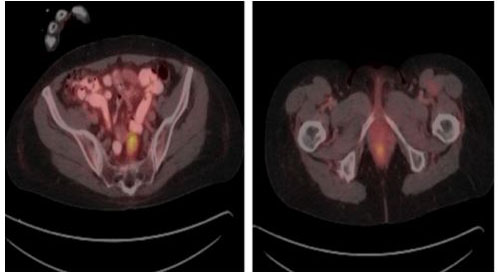

Staging computed tomography (CT) scan of the chest, abdomen, and pelvis with oral and intravenous contrast was negative for metastatic lesions but was significant for left iliac chain lymphadenopathy. A fluorodeoxyglucose positron emission tomography scan (FDG PET) was performed which demonstrated significant abnormal anal tracer uptake with SUV max 4.6 as well as tracer avid pelvic lymph nodes including presacral, medial to the left internal iliac vein tracer avid lymph nodes 2.5 1.5 cm with SUV max 6.2 as well as a left common iliac chain rounded lymph node 0.9 × 0.9 cm with SUV max 2.6, consistent with metastatic adenopathy (Figure 4).

Figure 4: PET/CT demonstrating tracer avid anal mass and pelvic lymphadenopathy.